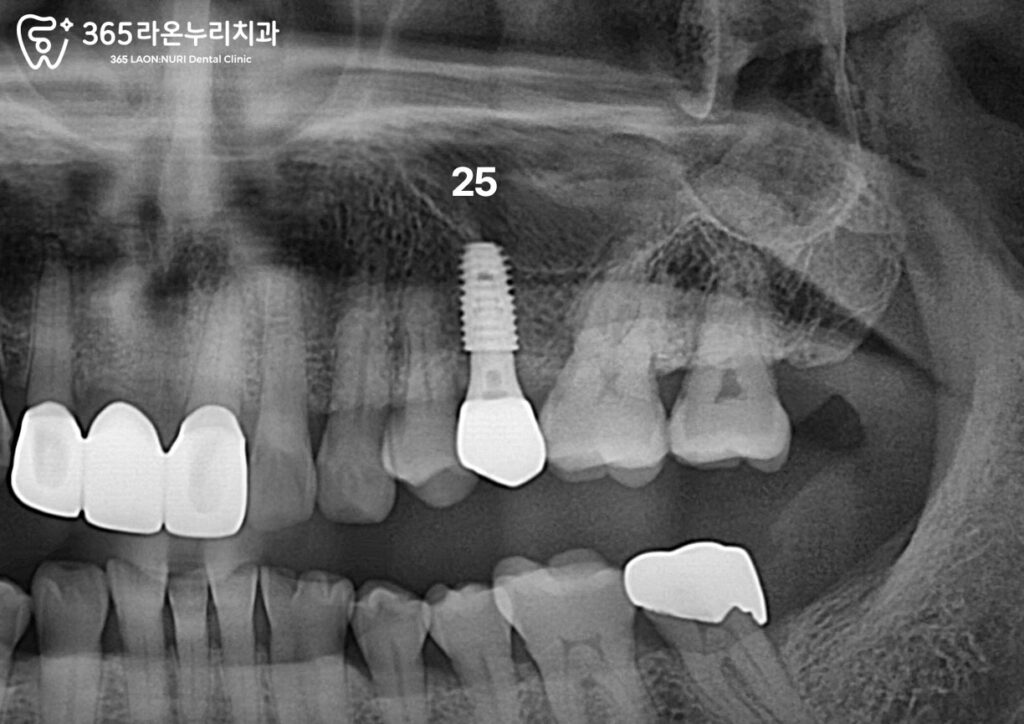

최종 보철 장착

치유와 완료되면 스캐너를 이용해

치아, 잇몸, 픽스처의 위치를

3차원으로 스캔합니다.

이는 맞춤형 보철을 더 빠르고

정확하게 제작할 수 있게 도와줍니다.

경계면에 미세한 틈이 있다면

2차 우식이나 임플란트 주위염이

일어날 위험이 증가하기 때문에

엑스레이를 통해 보철과

어버트먼트의 경계가 잘 맞는지,

미세한 틈이 없는지 확인합니다.

앞서 세교동 치과 에서 보여드린

임플란트를 심었던 25번 부위입니다.

16번과 마찬가지로 자연치와

유사한 색의 크라운이 사용되었습니다.